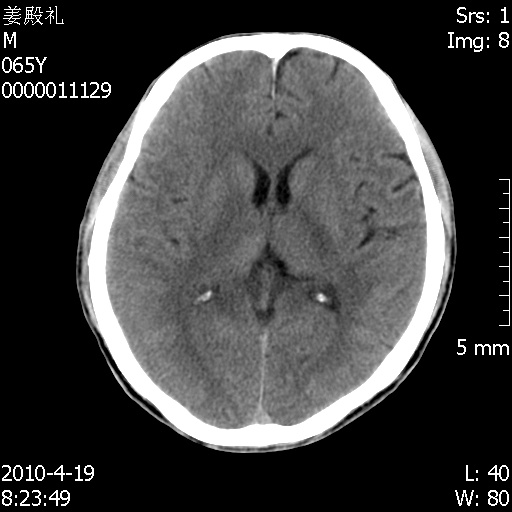

老年男性,突发左下肢无力1天,其余有价值的检查都没有。平扫ct值大约60hu,增强后ct值没什么改变,请大家讨论一下这个病例是什么?说明诊断理由。

左小脑、右大脑顶叶多发圆形高密度病灶,其周环状低密度影。考虑多发脑出血。隔期观察。

至于是出血还是微小钙化所致的高密度无法考证,三个都出血也不是一点都不可能,同一种组织学类型的肿瘤受到同一个外来的因素影响后会表现出相同的病理变化。说实在的,我本身支持转移瘤的,就是想不通为什么不强化?我认为单纯脑出血的边缘不会那么光滑,并且那也不是出血的常见部位,多发也不常见。

刚刚复习了转移瘤的不典型ct征象,有4条,分享给大家:

1、高密度灶:多为瘤内有较多沙粒体钙化所致,而不是出血,ct值可高达95hu;

2、无强化;

3、无水肿;

4、无占位效应。